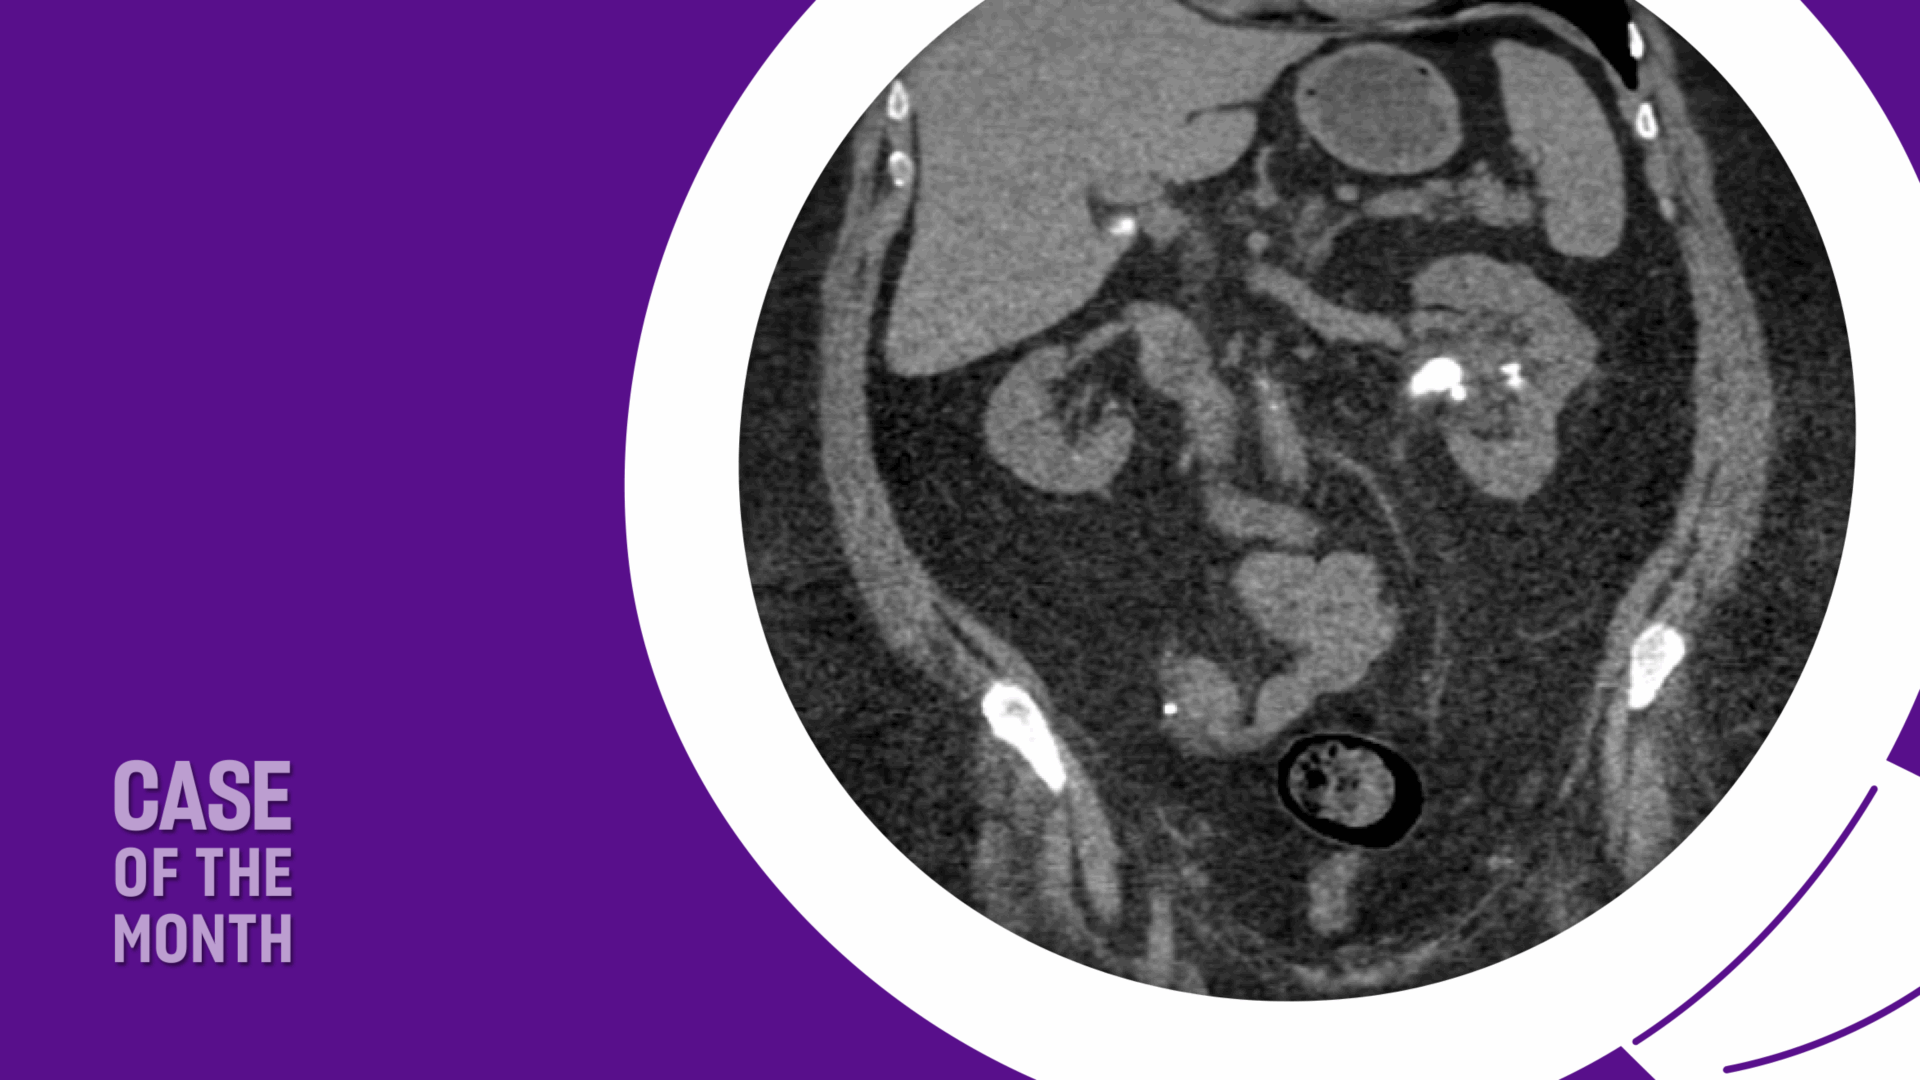

Non-contrast CT revealed mild left hydronephrosis, ureteropelvic junction stones measuring 15 x 7 x 14 mm and 9 x 9 mm, and a lower pole stone measuring 17 x 5 mm (Figure 1). The stones were not visible on CT scout or kidney, ureter, and bladder (KUB) X-ray, which could either be due to body habitus or uric acid composition.

Stone density measured 344 Hounsfield units, and urine pH over the prior year ranged from 5.5 to 6.0—findings consistent with uric acid stone composition. Serum creatinine was normal and potassium was normal-to-high at 4.9 mmol/L.